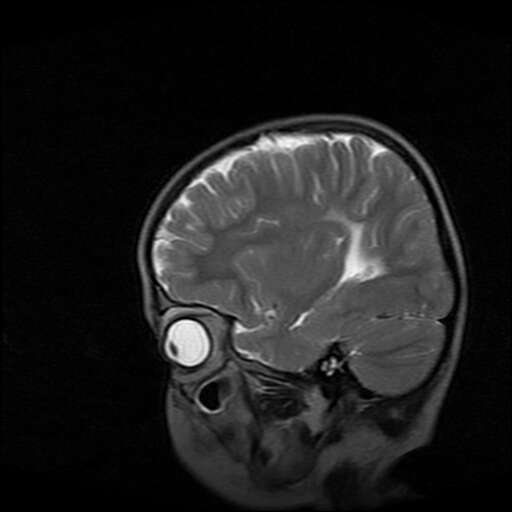

女,7岁,三岁才说话、走路。现智力尚可,走路不稳。临床怀疑大脑发育不全。

考虑胼胝体发育不全,髓鞘形成不良。

支持考虑胼胝体发育不全,髓鞘形成不良。

脑裂畸形伴灰质异位

侧脑室周围白质数量减少,侧脑室不对称性扩大,左侧侧脑室后角呈方形改变,脑沟加深,结合临床考虑脑室周围白质软化症(pvl)。期待结果!